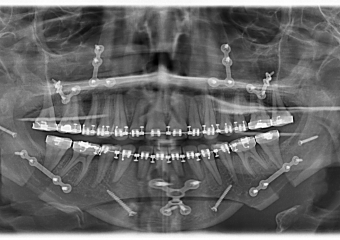

Raio x inicial

Raio x após a cirurgia realizada em 2015